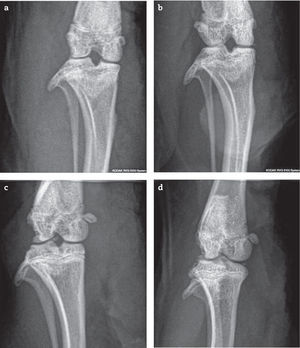

Las ratas que recibieron adyuvante presentaron, al día de la eutanasia, signos clínicos agudos de artritis con lesiones radiológicas manifiestas con compromiso subcondral. Las lesiones observadas fueron: pérdida de interlínea con disminución del espacio articular, deformación del cartílago articular y liberación de fragmentos articulares en todos los animales que recibieron adyuvante, tanto los grupos tratados como los controles. Además, se observó esclerosis y ligera osteofitosis (figs. 2 y 3).

Rayos X de articulación femorotibiorrotuliana en incidencia anteroposterior, a) basal, sin alteraciones (puntaje: 0) b) adyuvante + alendronato temprano (puntaje: 5): anormalidades en carilla articular, osteofitos y esclerosis subcondral. c) adyuvante + alendronato tardío (puntaje 6) presenta anormalidades del contorno óseo, cuerpo libre intrarticular y osteofitos. d) control adyuvante (puntaje: 5), osteofito, fragmento articular y esclerosis subcondral.

Los resultados radiográficos mostraron que todos los animales a los cuales se les indujo la artritis con adyuvante, desarrollaron signos graves independientes de los tratamientos con bifosfonatos. Por rayos X se pudo observar: inflamación de tejidos blandos, pérdida del contorno articular, formación de osteofitos, estrechamiento de la luz articular y fragmentos articulares. Estas lesiones coinciden con las lesiones radiográficas e histológicas descritas previamente en este modelo de artritis33,34.